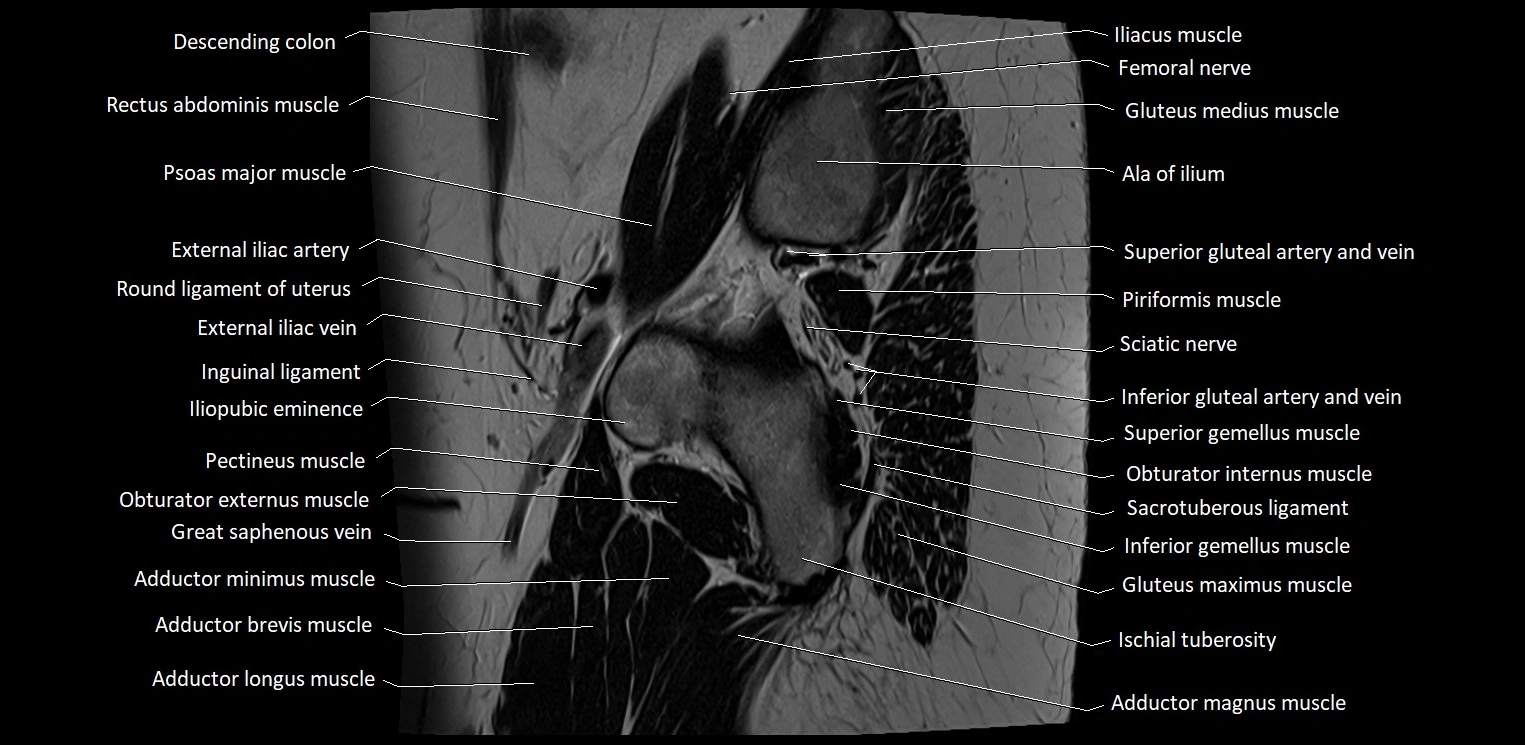

- Adductor brevis muscle

- Adductor longus muscle

- Adductor magnus muscle

- Adductor minimus muscle

- Ala of ilium (wing of ilium)

- External iliac artery

- External iliac vein

- Femoral nerve

- Gluteus maximus muscle

- Gluteus medius muscle

- Ileum

- Iliopubic eminence

- Inferior gemellus muscle

- Inferior gluteal artery

- Inferior gluteal vein

- Inguinal ligament

- Ischial tuberosity

- Obturator externus muscle

- Pectineus muscle

- Piriformis muscle

- Psoas major muscle

- Round ligament of uterus

- Sacrotuberous ligament

- Sciatic nerve

- Superior gemellus muscle

- Superior gluteal artery

- Superior gluteal veins

- great saphenous vein